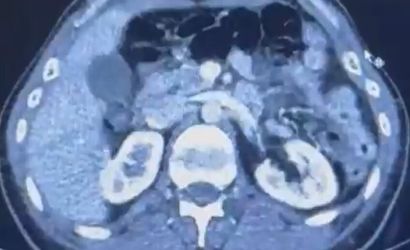

S.C. ve R.B.C.'nin Kayseri Şehir Hastanesi'nde yapılan iç beden muayenelerinde, mide bölgesinde 50 adet kapsül halinde toplam 554 gram uyuşturucu madde tespit edildi.

ŞÜPHELİLERİN MİDESİNDE KAPSÜL ŞEKLİNDE YARIM KİLO UYUŞTURUCU MADDE ELE GEÇİRİLDİ.